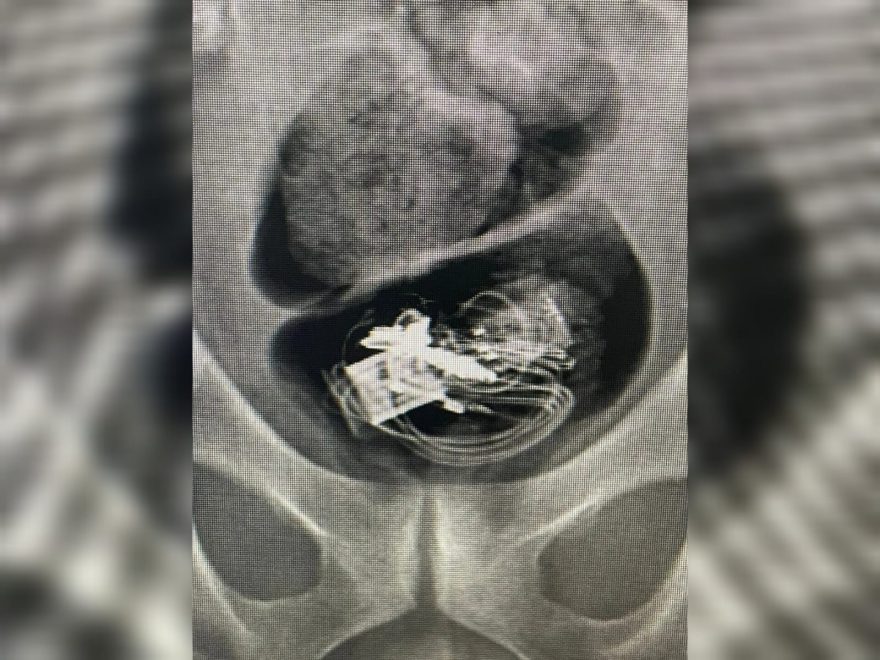

Na sequência, já na delegacia, ele confessou que engoliu os itens com a intenção de comercializá-los dentro da cadeia. Um exame de raio-x confirmou a presença dos objetos no intestino dele. Ele acabou preso, mas foi colocado em área isolada do presídio e com monitoramento para poder expelir os itens engolidos.